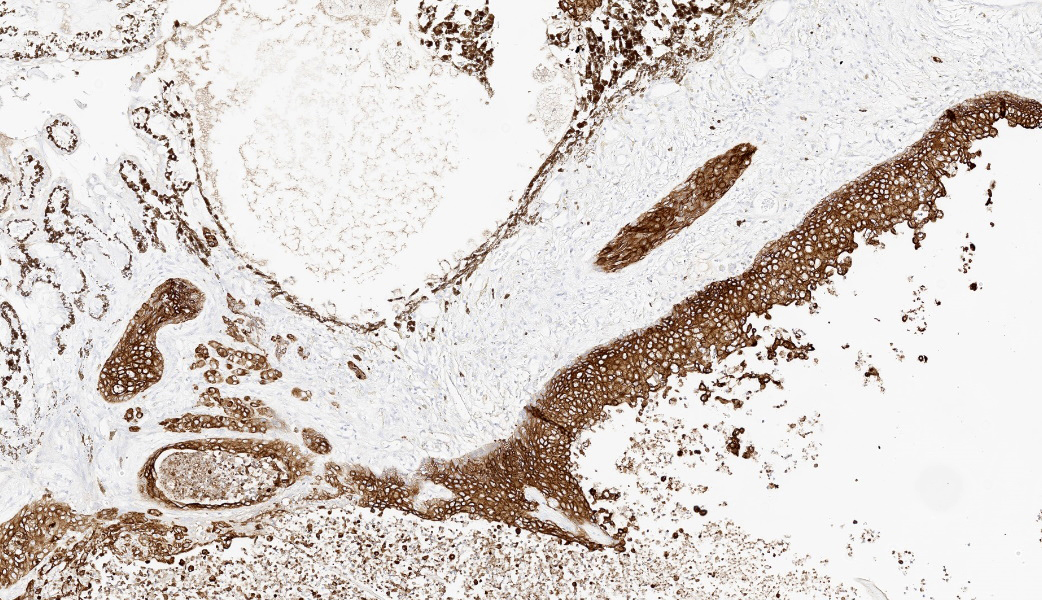

In keeping with her “games” theme, MAJ Fiddes put participants through a few rounds of “I Spy” during this case, focused entirely on the pancytokeratin (AE1/AE3) immunohistochemical stain run on this case and a few issues spotted therein. The first issue was that, while the neoplastic cells had strong cytoplasmic immunoreactivity to pancytokeratin, the retinal pigmented epithelium (RPE) was diffusely unreactive. As it turns out, RPE is specifically reactive for CK8/18, and the pancytokeratin cocktail used by the JPC does not include these. Instead, CK8/18 is offered as a stand-alone IHC here, and its absence in the pancytokeratin would explain why the RPE was not reactive. The second issue was that the neural fibers of the optic nerve had diffuse reactivity to pancytokeratin. That’s weird, why would neural tissue be reactive to cytokeratins? Well, as fate would have it, it’s not. Pancytokeratin and GFAP are cross-reactive. GFAP is not cross-reactive with most individual cytokeratins, but is to pancytokeratin, making neural tissue appear immunoreactive to AE1/AE3!3 Between AE1 and AE3, it is the AE3 component specifically that contributes to this cross-reactivity.3 This has been demonstrated in brain and glial tissues, as well as in some retroperitoneal schwannomas. As such, interpretation of cytokeratin expression in neural tissue, including neoplasms of neural origins, should be cautiously interpreted.3 This “I Spy” game was a poignant reminder that pathologists should scrutinize IHCs and ensure good external and internal control prior to reading them out, and knowledge of what reacts to what can be critical to appropriate interpretation.